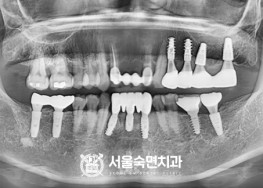

임플란트-치료-전후사진